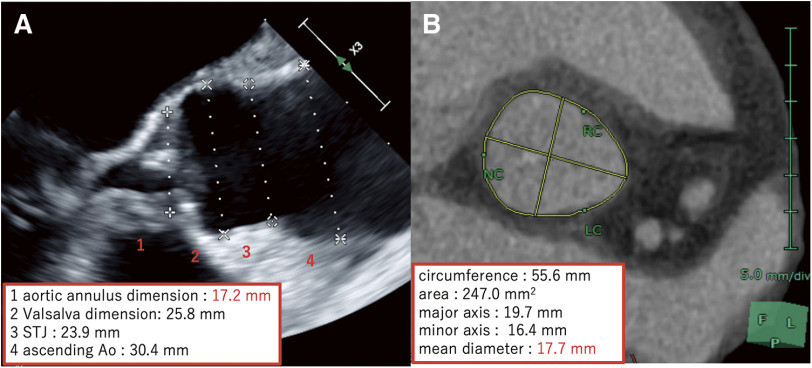

Bo博士在2021年推出的Y形切口技术是一种非常创新的技术,可以在不侵犯左心房或二尖瓣的情况下将主动脉瓣环扩大两个或两个以上的尺寸。然而,我们遇到了一个病例,其中左冠状动脉口位于左侧非连合附近。因此,我们认为将切口扩大到左冠状动脉环是危险的。因此,我们设计了一种新技术,只以“L”方式而不是“Y”方式放大非冠状环。在进行该手术时,术前三维图像有助于在计划主动脉环扩大手术时了解解剖结构。L形切口技术可能是主动脉瓣环扩大的一种有用的替代方法。

The Y-incision technique introduced by Dr. Bo Yang in 2021 is a very innovative technique that can enlarge the aortic annulus by two or more sizes without violating the left atrium or mitral valve. However, we encountered a case in which the left coronary artery ostium was located close to the left-non commissure. Therefore, we considered it would be dangerous to expand the incision to the left coronary annulus. We therefore devised a new technique that enlarges only the noncoronary annulus in an "L" fashion instead of a "Y" fashion. In performing this surgery, preoperative three-dimensional images were useful for understanding the anatomy when planning the aortic annular enlargement procedure. The L-incision technique can be a useful alternative method of aortic annulus enlargement.